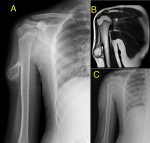

A 16-year-old boy presented with a painless, hard swelling over the lateral aspect of his right upper arm. There was no history of trauma, constitutional symptoms, or functional limitations. On clinical examination, the mass was firm and nontender. Radiography of the right upper limb revealed a solid, irregular outgrowth of the right humerus (A). Magnetic resolution imaging (MRI) revealed a bony outgrowth arising from the lateral aspect of the diaphysis of the right humerus, suggestive of a pedunculated osteochondroma (B). Owing to cosmetic concerns and the potential risk of neurovascular compression, surgical excision was performed. Histopathological examination confirmed a benign osteochondroma with no evidence of malignant transformation. The postoperative radiography revealed cosmetic improvement (C) and the patient remained asymptomatic. This case underscores the importance of recognising osteochondroma as a common benign entity in adolescents, while also considering the need for surgical intervention in symptomatic or cosmetic cases. Early imaging and appropriate management can prevent complications, particularly in lesions with atypical growth or proximity to vital structures.

Figure 1: A) right humerus showing irregular outgrowth; B) T2-weighted MRI of right humerus showing bony outgrowth arising from the lateral aspect of diaphysis; C) postoperative radiography showing cosmetic improvement